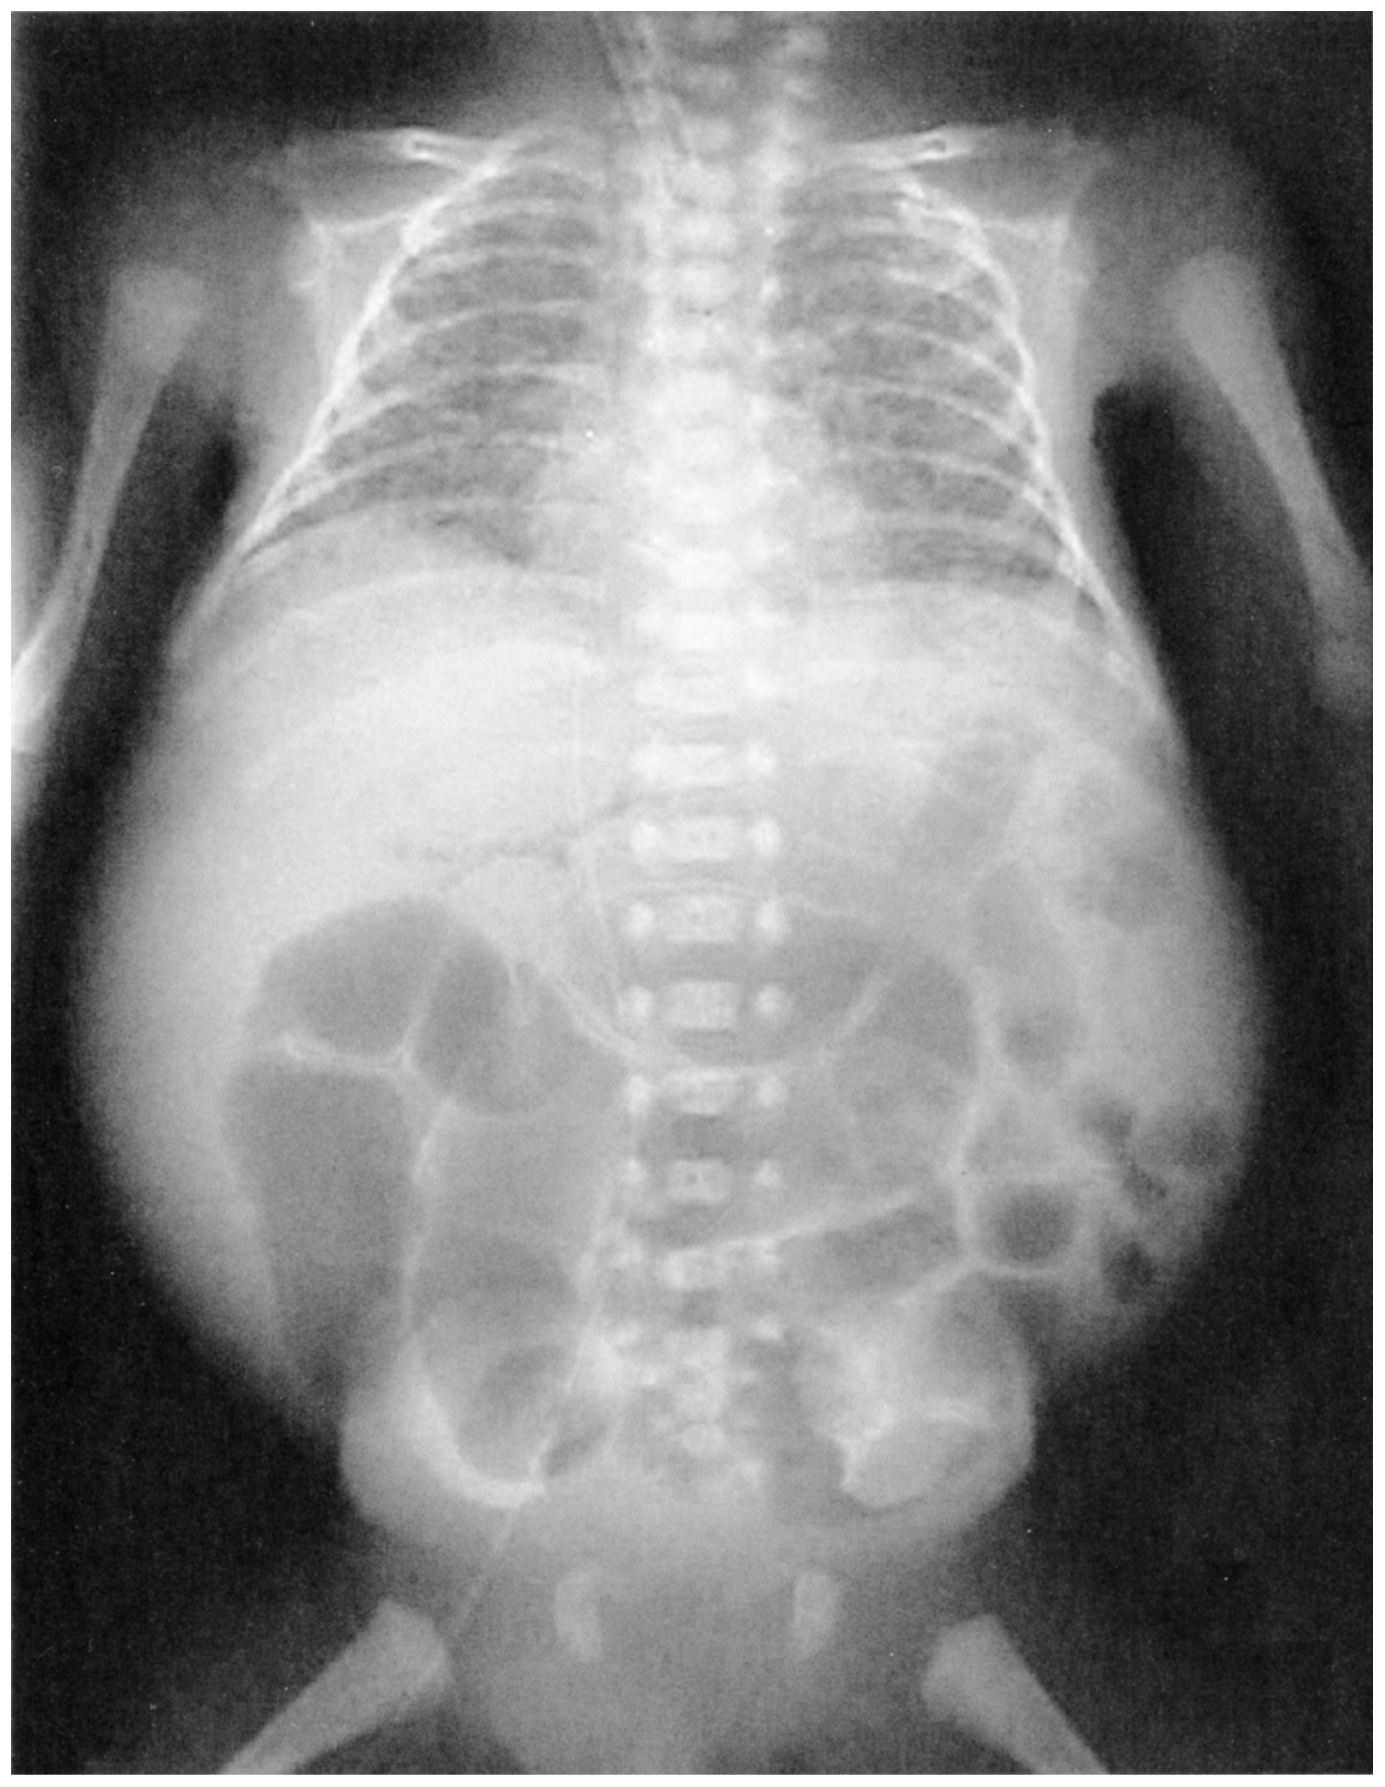

日齢15の男児。NICU入院中に看護師が血便に気付いたため医師に報告した。在胎26週,前期破水のために緊急帝王切開で出生した。出生後すぐに気管挿管され,保育器内で人工呼吸管理を行われていた。栄養は人工乳を経鼻胃管から注入され,排便も1日2回はみられていた。今朝,経鼻胃管から胆汁を混じた胃液が10mL吸引された。身長32cm,体重830g。体温37.2℃。心拍数180/分,整。血圧46/24mmHg。呼吸数40/分(呼吸器設定:換気回数40/分,FIO2 0.25)。SpO2 96%。腹部膨隆を認め,腫瘤は触知せず,腹壁の色は暗赤色であった。血液所見;赤血球317万,Hb 12.1g/dL,Ht 37%,血小板12万。静脈血ガス分析:pH 7.17,PCO2 55 Torr,HCO3 20mEq/L。胸腹部エックス線写真を下に示す。